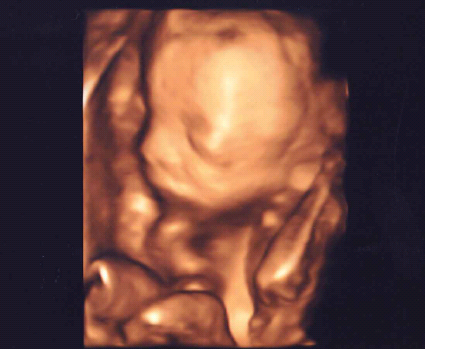

Mein kleiner Prinz ist soooooo hübsch. Er wiegt jetzt ca. 450 Gramm und hat ganz niedlich mit seinen Füßchen gespielt. Werte waren auch alle bestens und er ist zeitgerecht entwickelt. Hab in den letzten 4 Wochen nur 1 Kilo zugenommen, seit Beginn der Schwangerschaft jetzt insgesamt 2,5 Kilo Hier noch ein Foto von meinem kleinen Schatz:

Bild zu Zurück vom FA und sooooo verliebt! - Forum für April - Mamis